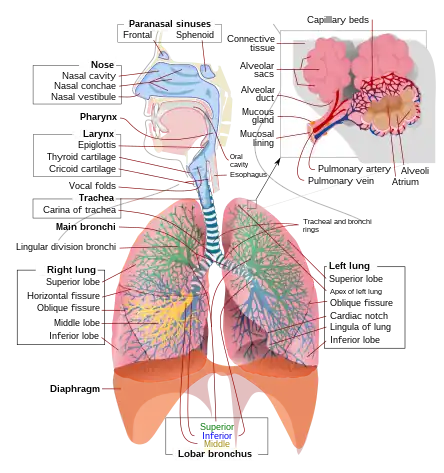

Medicine is the science and practice of caring for a patient, managing the diagnosis, prognosis, prevention, treatment, palliation of their injury or disease, and promoting their health. Medicine encompasses a variety of health care practices evolved to maintain and restore health by the prevention and treatment of illness. Contemporary medicine applies biomedical sciences, biomedical research, genetics, and medical technology to diagnose, treat, and prevent injury and disease, typically through pharmaceuticals or surgery, but also through therapies as diverse as psychotherapy, external splints and traction, medical devices, biologics, and ionizing radiation, amongst others.

The following are images from various Medicine-related articles on Wikipedia.